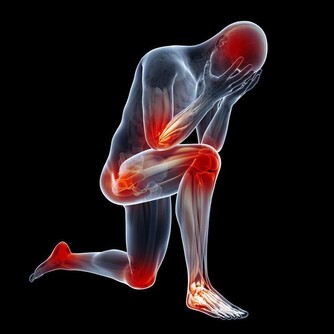

隨著年齡增長,很多人筋骨不如從前了,爬個樓、登個高,很容易就感覺關節痛。

特別是這個季節,天氣轉冷,更是動不動就膝蓋疼。

跟很多中老年人一樣,國醫大師年老時,也遇到了這樣的問題,上下樓梯時,都感到膝蓋疼。